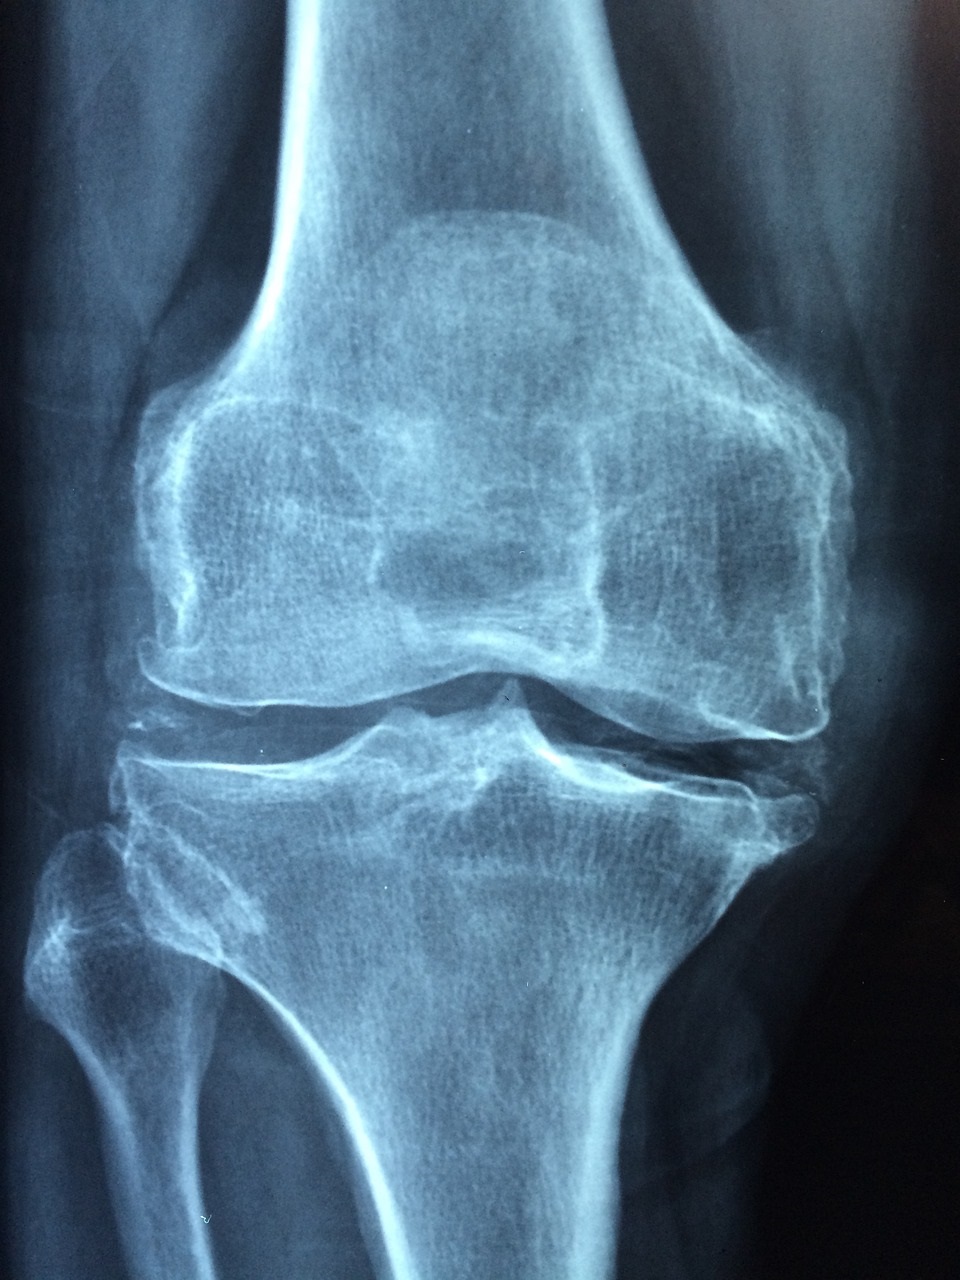

골다공증은 일반적으로 노년기에 나타나는 질병으로 인식되지만, 사실 그 기초는 40대부터 이미 형성되기 시작합니다. 특히 여성은 폐경기를 전후로 여성호르몬인 에스트로겐이 급감하게 되면서 골밀도 감소가 가속화되므로 조기 예방이 매우 중요합니다. 골다공증은 뼈의 밀도가 낮아져 쉽게 부러지는 상태를 말합니다. 초기에는 자각 증상이 거의 없기 때문에 "침묵의 질병"이라고 불리며, 대부분 골절이라는 사고로 처음 발견되는 경우가 많습니다. 손목, 척추, 고관절 골절이 대표적이며, 40대 이후 넘어지거나 가벼운 충격에도 뼈가 부러지는 일이 발생할 수 있습니다. 다음과 같은 경우 골다공증 위험이 증가합니다: - 폐경기 진입 - 칼슘, 비타민 D 부족 - 운동 부족 - 저체중 - 가족력 특히 칼슘이 풍부한 음식을 적게 먹거나 유제품을 꺼리는 식습관, 실내 위주의 생활 방식 등은 40대 여성의 골밀도 감소에 큰 영향을 미칩니다. 또한 최근에는 야외 활동 부족으로 비타민 D 결핍도 심각한 문제가 되고 있습니다. 비타민 D는 칼슘 흡수를 도와주는 중요한 영양소이므로 충분한 햇볕 노출과 보충제가 필요합니다. 예방을 위해서는 칼슘이 풍부한 식품(우유, 멸치, 치즈, 브로콜리 등)을 섭취하고, 주 2~3회 걷기나 가벼운 근력 운동을 하는 것이 효과적입니다. 골밀도 측정검사(DXA)를 2년에 한 번씩 정기적으로 받는 것도 조기 진단에 도움이 됩니다. 조기에 발견하면 약물치료와 영양조절로 충분히 관리가 가능합니다.